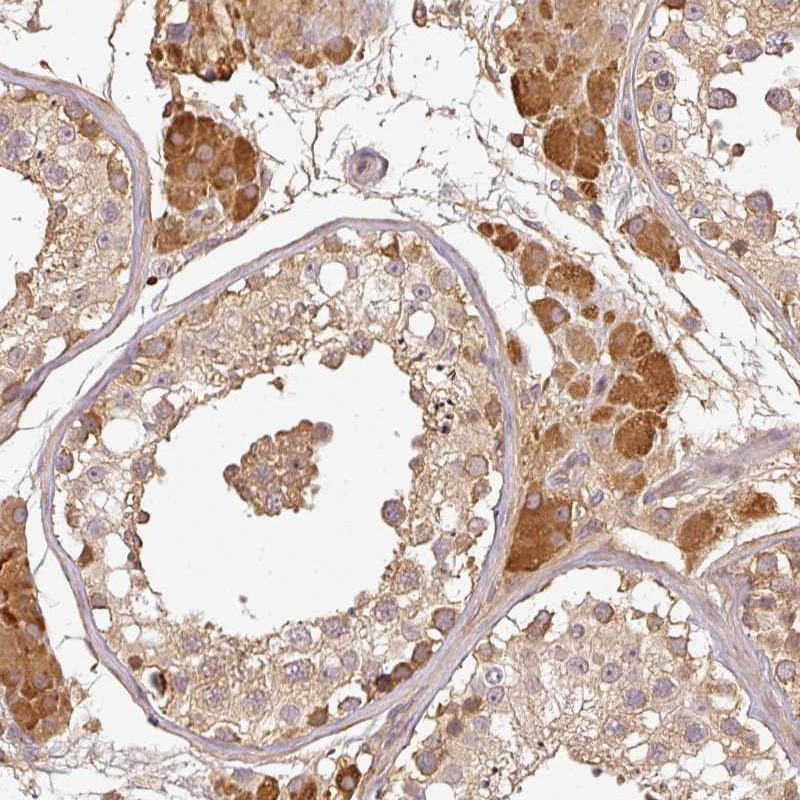

Immunohistochemical staining of human testis shows moderate cytoplasmic positivity in cells in seminiferous ducts, Leydig cells were strongly stained.